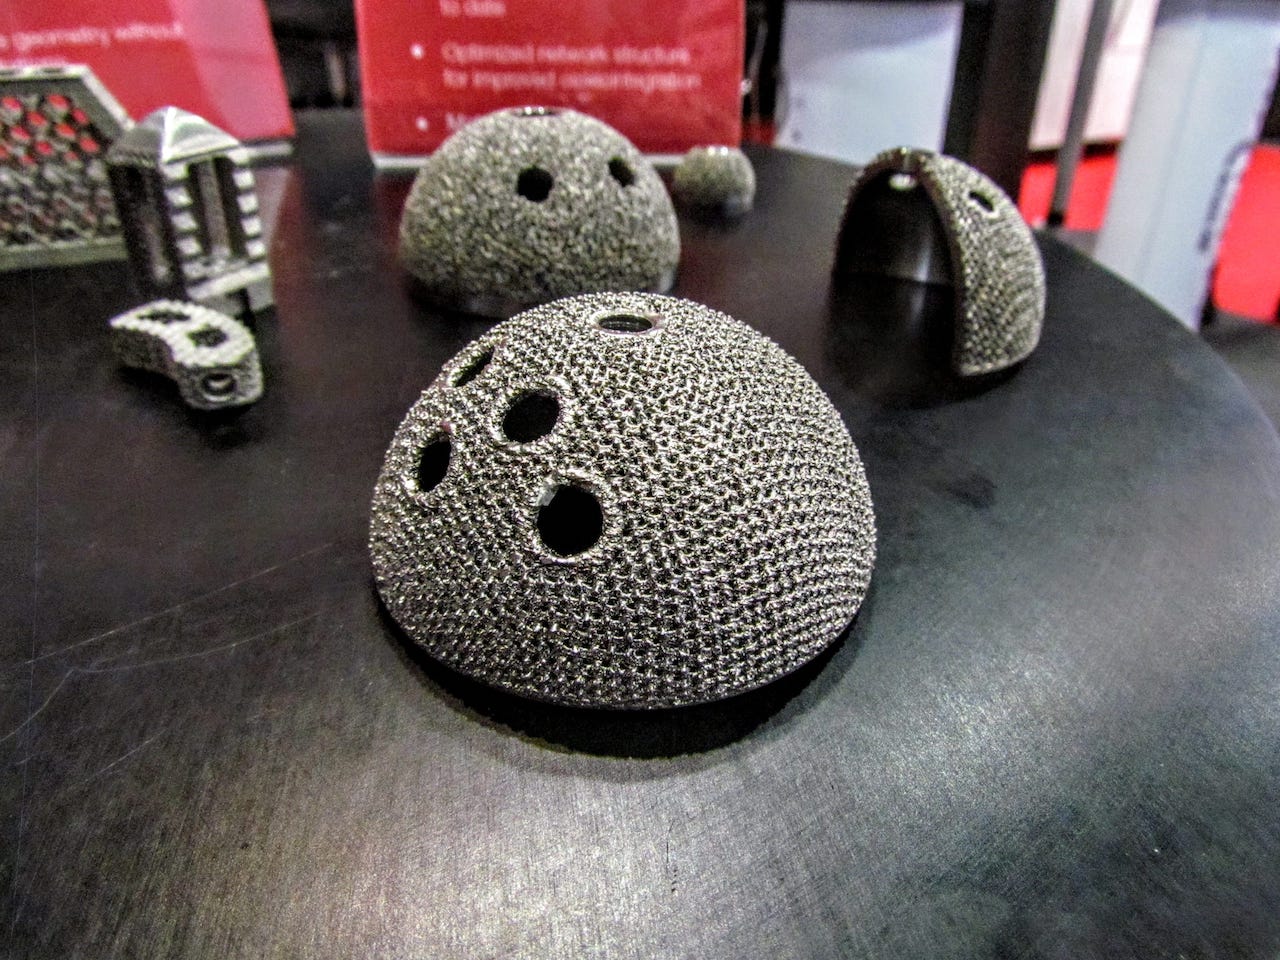

Materialise Mimics inPrint Certification Program Clears Ultimaker and Formlabs for Medical 3D Printing

Materialise’s announcement today of FDA-cleared medical model 3D printing encompasses vat polymerization and material extrusion technologies in addition to PolyJet.

FDA-Cleared Medical 3D Printing with Stratasys and Materialise

3D printing medical models offers benefits to patients and those providing their care with highly accurate patient-specific anatomies able to be held, examined, and practiced on.